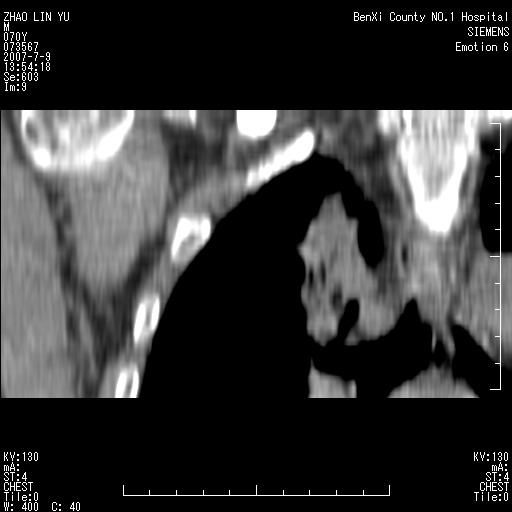

以下是引用王靖旗在2007-7-10 17:12:00的发言:[br] 男、70、咳嗽两个月,半年前换瓣手术,胸片未见异常,于昨天行x片发现右肺上野大片影,行ct扫描,这里是减薄图像,余肺正常。明天晚上会有增强扫描片,到时我会上传。[br][br] 冠状位请大家细看,应该是有意义的,[br][br] 请大家先看平扫发表意见。[br][br]

[br]冠状面[br]

以下是引用zhangzhongshou在2007-7-10 21:43:00的发言:[br]右肺上叶周围型肺癌,以孤立型细支气管肺泡癌可能性大。